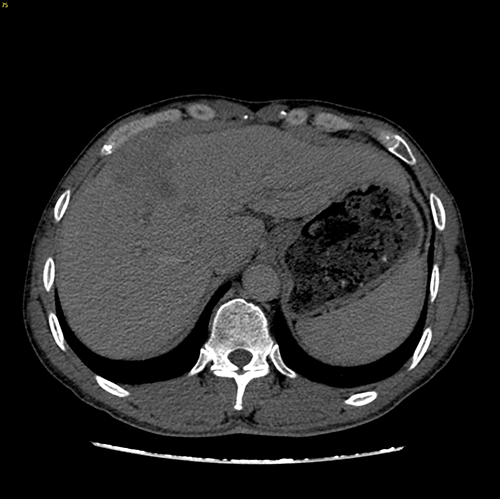

右肝癌---右三肝切除

介入后2周